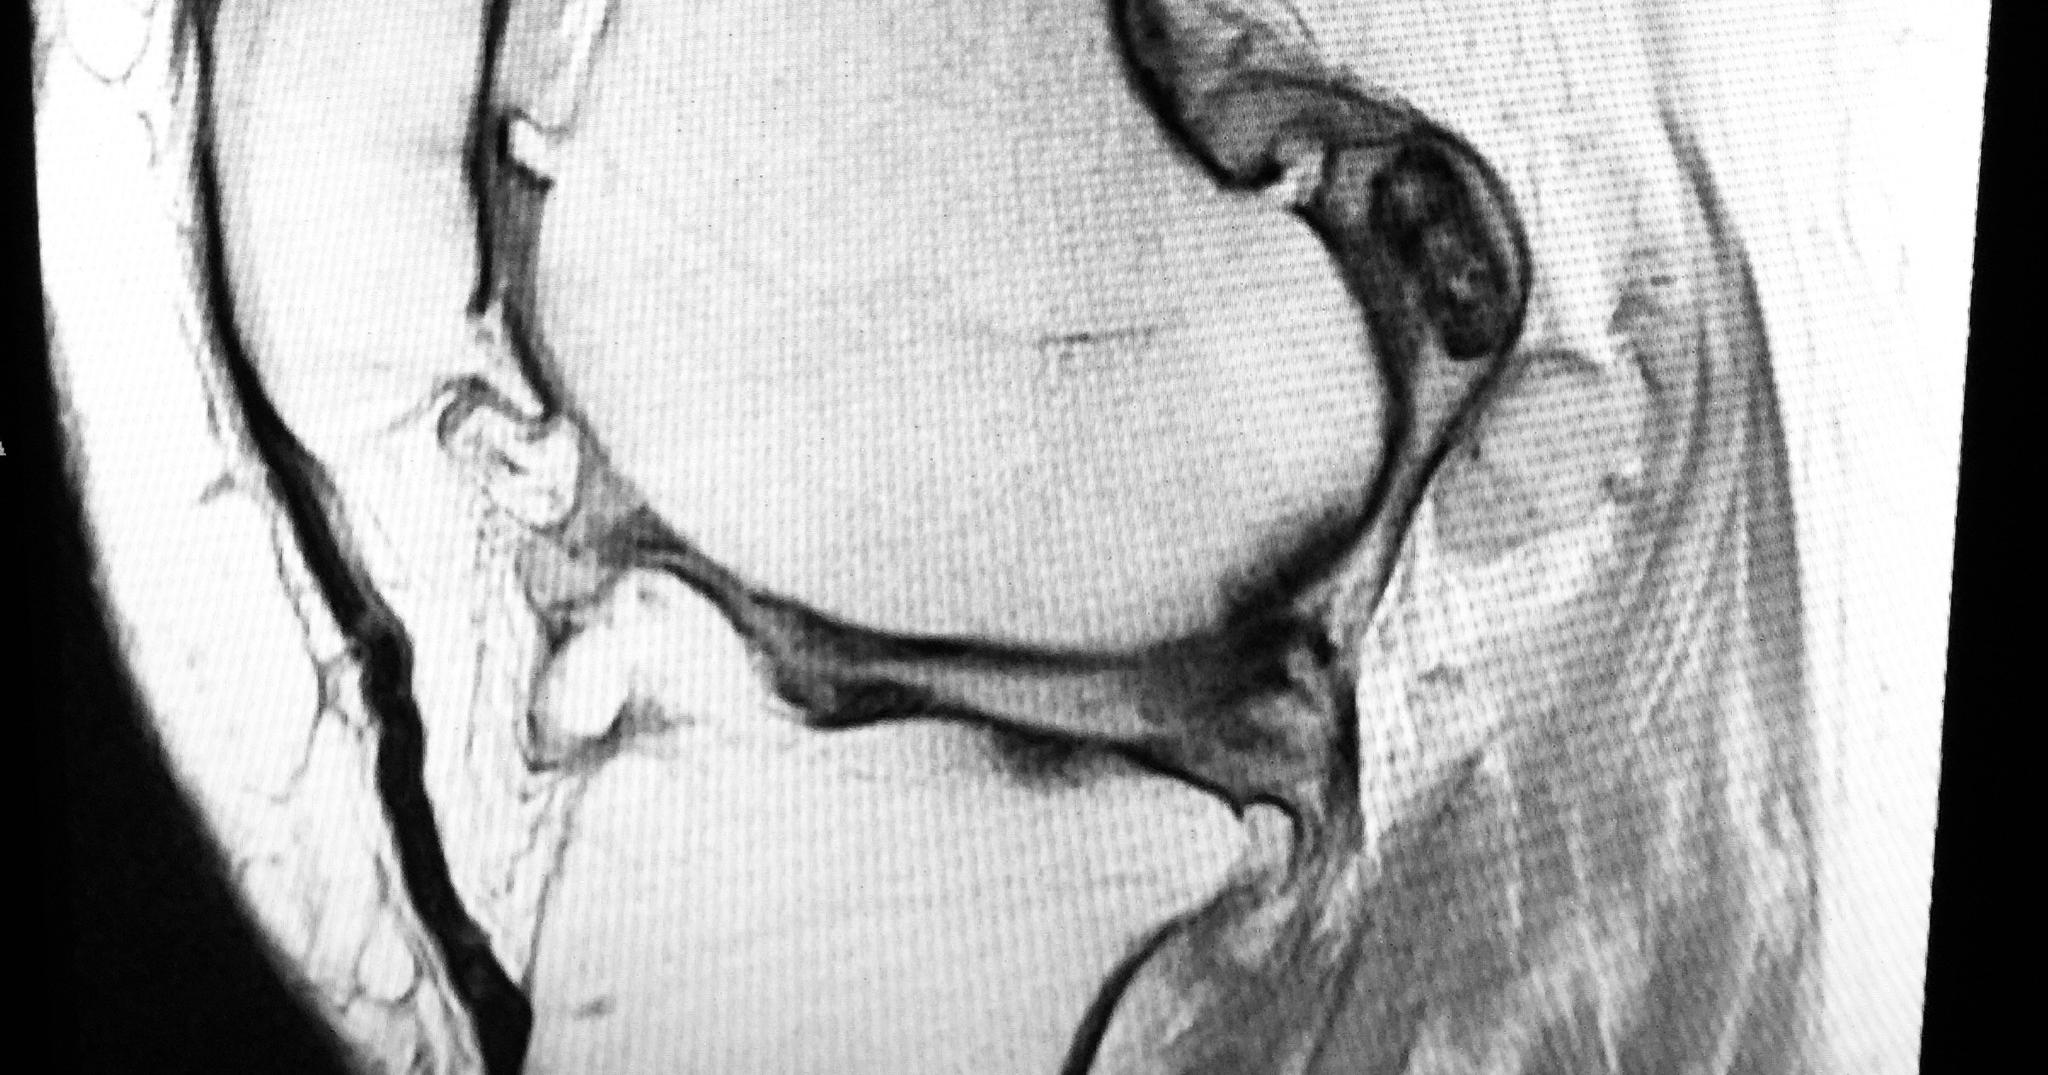

1. Joint Effusion

Often the earliest sign, joint effusion is when fluid begins to form around a joint. Although noticeable, the amount of fluid is fairly small. In some cases, when infection occurs, pus is released. Doctors can study this fluid to determine the cause, as a cloudy fluid with a golden color could indicate gout. Since cloudy fluid is associated with increased white blood cells, a sample could also indicate infection. Luckily, this fluid can be drained and then effective management strategies can be implemented. Follow these strategies in order to reduce the future accumulation of joint fluid.